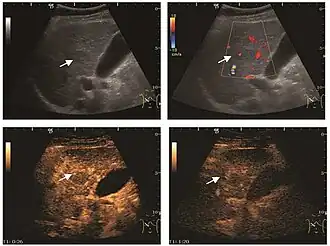

US examination is required to detect liver metastases in patients with oncologic history. In addition, the method can incidentally detect metastases in asymptomatic patients. Early identification (small sizes, small number) is important to establish an optimal course of treatment which can be complex (chemotherapy, radiofrequency ablation, surgical resection) but welcomed. In addition, discrimination of synchronous lesions that have a different nature is also important knowing that up to 25–50% of liver lesions less than 2 cm detected in cancer patients may be benign . US sensitivity for metastases detection varies depending on the examiner's experience and the equipment used and ranges between 40 and 80% . Sensitivity is conditioned by the size and acoustic impedance of the nodules. For a lesion diameter below 10 mm US accuracy is greatly reduced, reaching approx. 20%. Other elements contributing to lower US performance are: excessive obesity, fatty liver disease, hypomobility of the diaphragm, and certain patterns of hyperechoic or isoechoic metastases that can be overlooked or can mimic benign conditions. Conventional US appearance of metastases is uncharacteristic, consisting of circumscribed lesions, with clear, imprecise or "halo" delineation, with homogeneous or heterogeneous echo pattern. They can be single (often liver metastases from colonic neoplasm) or multiple. Echogenity is variable. When increased, they can compress the bile ducts (which may be dilated) and the liver vessels. Liver involvement can be segmental, lobar or generalized. In this situation a pronounced hepatomegaly occurs. Generally, metastases have non-characteristic Doppler vascular pattern, with few exceptions (carcinoid metastases). Cyst-adenocarcinoma metastases due to semifluid content may have a transonic appearance. When increasing, they can result in central necrosis. CEUS examination is a real breakthrough for detection and characterization of liver metastases.

Increased performance is based on identifying specific vascular patterns during the arterial phase and seeing metastases in contrast to normal liver parenchyma during the sinusoidal phase. CEUS increased accuracy is due to the different behavior of normal liver parenchyma (captures CA in Kuppfer cells) against tumor parenchyma (does not contain Kuppfer cells, therefore CEUS appearance is hypoechoic). To this adds the particularities of intratumoral circulation represented by a reduced arterial bed compared to that of the surrounding normal liver and the absence of the portal vessels . In terms of vascularity, metastases can be hypovascular (in gastric, colonic, pancreatic or ovarian adenocarcinomas) with hypoechoic pattern during arterial phase, and similar during portal venous and late phases, respectively hypervascular (neuroendocrine tumors, malignant melanoma, sarcomas, renal, breast or thyroid tumors) with hyperechoic appearance during arterial phase, with washout during the portal venous phase and hypoechoic pattern 30 seconds after injection.